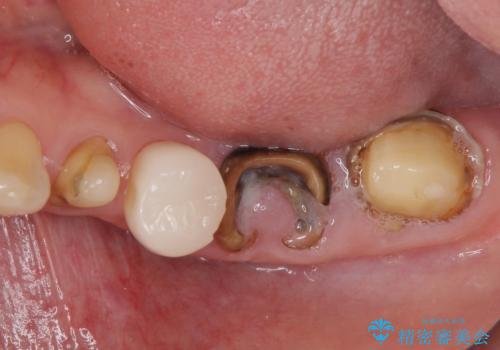

- 虫歯や歯の欠損を放置していることを気にして来院された患者様です。

下顎には抜歯が必要な歯があったため、抜歯後に治癒を待ち、上顎とともにオールセラミックブリッジにて補綴治療を行うこととしました。